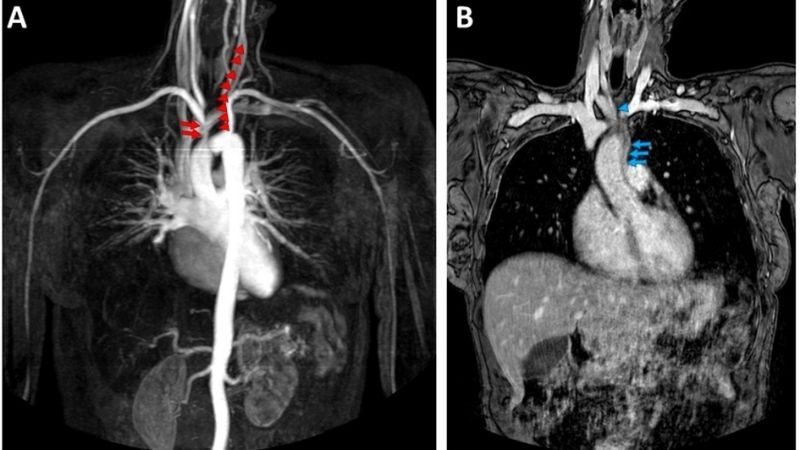

Takayasu's arteritis diagnosis with imaging tests

Images visual examples of Takayasu's arteritis

Takayasu's arteritis is a rare chronic inflammatory disease affecting large blood vessels, particularly the aorta and its branches, leading to narrowing and reduced blood flow.